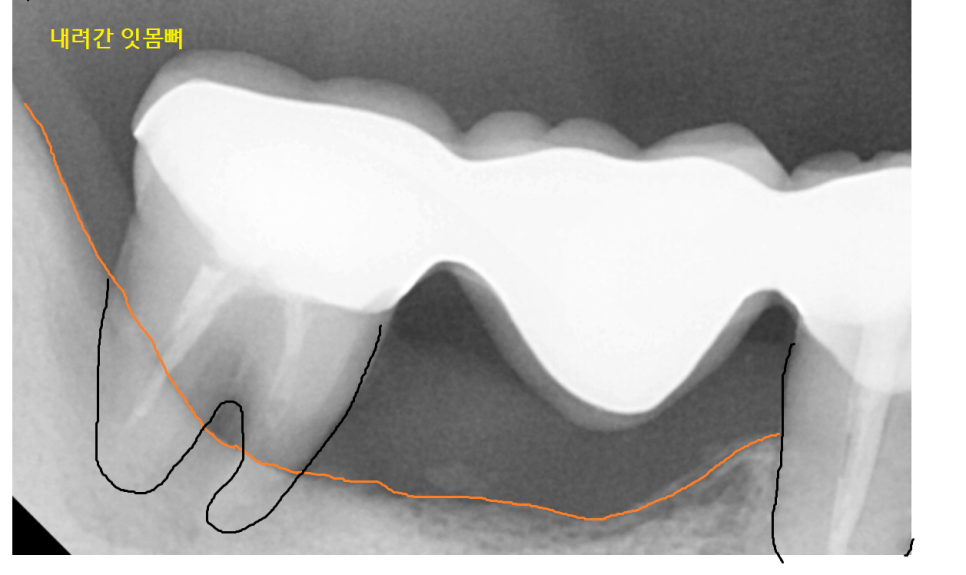

오래전 브릿지로 씌워둔 치아가

수명을 다했네요.

잇몸뼈가 많이 녹아서

뿌리 끝부분만 붙잡고 있는 게 보이시죠~?

보철물 아래쪽으로 음식물도 끼고

불편하셨겠어요.